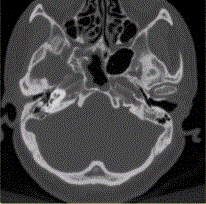

问题 患者男,20岁,外伤后右耳听力下降伴面瘫7d。临床检查,右耳传导性耳聋,发现脑脊液耳瘘。CT表现如下图。 颞骨HRCT的主要技术参数不包括

选项 A.薄层扫描(1~2mm) B.重建矩阵不低于512×512 C.骨重建算法 D.小扫描野或靶扫描 E.高mA扫描

答案 E